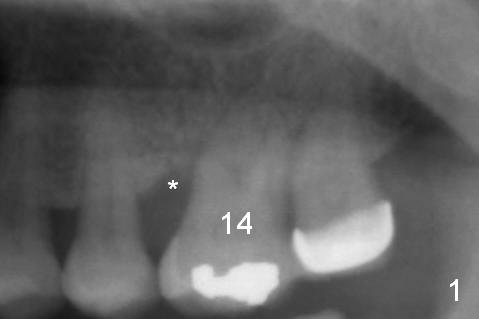

A 54-year-old woman has history of chronic periodontitis with bruxism. Bone loss at the tooth #14 starts at the mesial crest (Fig.1: 2008), extends to the mesial root (Fig.2, 2015) and the palatal one (Fig.3, 2016). The periodontal pockets are deep with mobility III. Since the defect is large with low bone density, Magic osteotomes are going to be used for CMC immediately after extraction (Clindamycin). If there is no history of sinusitis, a 11 mm long implant will be placed (Fig.4). Allograft (.5-1.5 mm) will be delivered with the large bone carrier for CMC (prior to implant placement) and the amalgam carriers for socket gap closure (before and after implant placement).